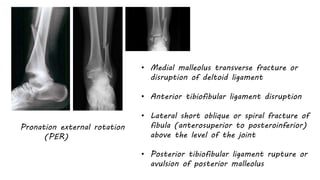

Pronation external rotation

(PER)

• Medial malleolus transverse fracture or

disruption of deltoid ligament

• Anterior tibiofibular ligament disruption

• Lateral short oblique or spiral fracture of

fibula (anterosuperior to posteroinferior)

above the level of the joint

• Posterior tibiofibular ligament rupture or

avulsion of posterior malleolus

Pronation external rotation (PER) •Medial malleolus transverse fracture or disruption of deltoid ligament • Anterior tibiofibular ligament disruption • Lateral short oblique or spiral fracture of fibula (anterosuperior to posteroinferior) above the level of the joint • Posterior tibiofibular ligament rupture or avulsion of posterior malleolus